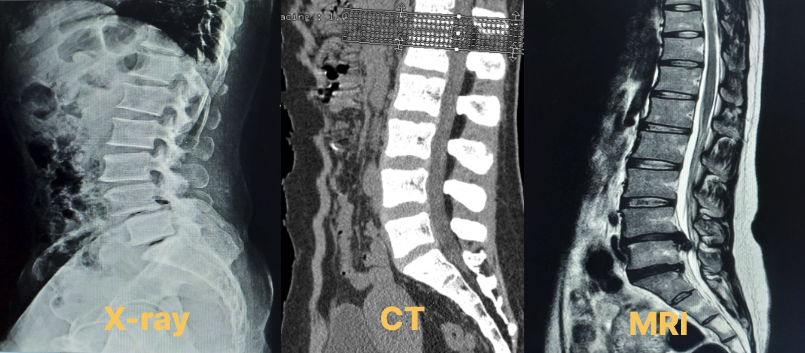

[ X-ray, CT, MRI 한번에 비교하기 ]

디스크 검사를 처음 받으러 가신다면

X-ray, CT, MRI를 찍게 되실거에요

그런데, X-ray, CT, MRI의 차이점은 뭘까요?

1. 단순 방사선 검사(X-ray)

1) 뼈의 구조를 전반적 구조를 볼 수 있습니다.

2) 디스크의 파열 정도나 인대 같은 연부 조직은 보이지 않기 때문에

디스크의 상태를 알기 위해서는 CT나 MRI가 필요하답니다.

* X-ray로 확인할 수 있는 것 :

뼈의 구조, 척추의 정렬, 골절, 인대의 골화, 석회 침착

2. 컴퓨터 단층 촬영 (CT)

1) 뼈의 손상을 볼 때, 폐 그리고 가슴, 복부 등의

출혈, 암을 확인하기에 적합한 검사예요.

2) CT는 방사선을 사용하기에 장시간 반복적으로 노출되면 유해할 수 있으나

가격이 MRI에 비해 저렴하고 빠르게 촬영을 할 수 있어요

* CT로 확인할 수 있는 것 :

정밀한 골절 진단, 인대의 석회화, 뼈의 구조, 척추의 측면 뿐만아니라

단면도까지 확인할 수 있답니다.

3. 자기 공명 촬영 (MRI)

1) MRI는 방사선을 쓰지 않는다는 장점이 있으나 가격이 비싸고 오래 걸려요.

2) 방사선 노출이 거의 없는 것이 특징이에요.

* MRI로 확인할 수 있는 것 :

디스크의 구조, 신경을 누르는 정도,디스크의 퇴행(탈수)여부,

디스크의 상태 및 척수ㆍ신경 압박 정도, 인대, 근육 같은 연부 조직,

종양의 유무,척추의 측면 뿐만아니라 단면도 등을 볼 수 있어요.

4. X-ray, CT, MRI 한번에 비교하기

X-ray, CT, MRI 차이가 보이시나요?

나의 증상에 따라 적절한 촬영으로 나의 상태를 확인해보세요.